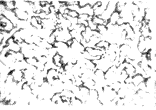

2.2 TUNEL法检测结果 组织切片中的凋亡细胞经TUNEL法染色后可见细胞核呈蓝紫色。Sham组(A)和TUENL阴性对照均无显著阳性细胞核(凋亡指数<5%),未经药物处理组(B)凋亡显著(心肌细胞凋亡指数67%±5%,与A组比较P<0.01),而经NAC处理组(C)阳性细胞核数明显减少(38%±3%,与B组比较P<0.01)(见图1)。

Sham组(A) 缺血再灌注组(B)无药物保护 缺血再灌注组(C),经NAC预处理

图1 TUNEL染色结果(目镜×20)